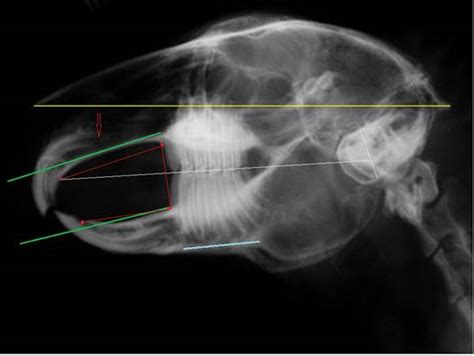

En la consulta esta indicada la realización de una radiografía para valorar el grado de lesión que presenta el animal. En la radiografía se observa sobrecrecimiento dental de los molares, tanto la raíz como de la corona dental, con afectación ósea de la mandíbula. Se aprecia también fractura de algunos de los dientes afectados por el sobrecrecimiento.

Radiografía de sobrecrecimiento dental en conejo